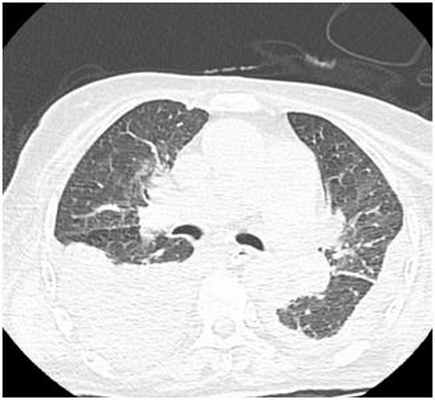

ИНСТРУМЕНТАЛЬНАЯ ДИАГНОСТИКА

К инструментальным методам диагностики в первую очередь относится рентгенография органов грудкой клетки, однако данный метод может быть неинформативным при малых объемах плеврита (до 500 мл), поэтому к дополнительным методам инструментальных исследований относятся УЗИ плевральных полостей и КТ органов грудной клетки.

Двусторонний гидроторакс (компьютерная томография органов грудной клетки)